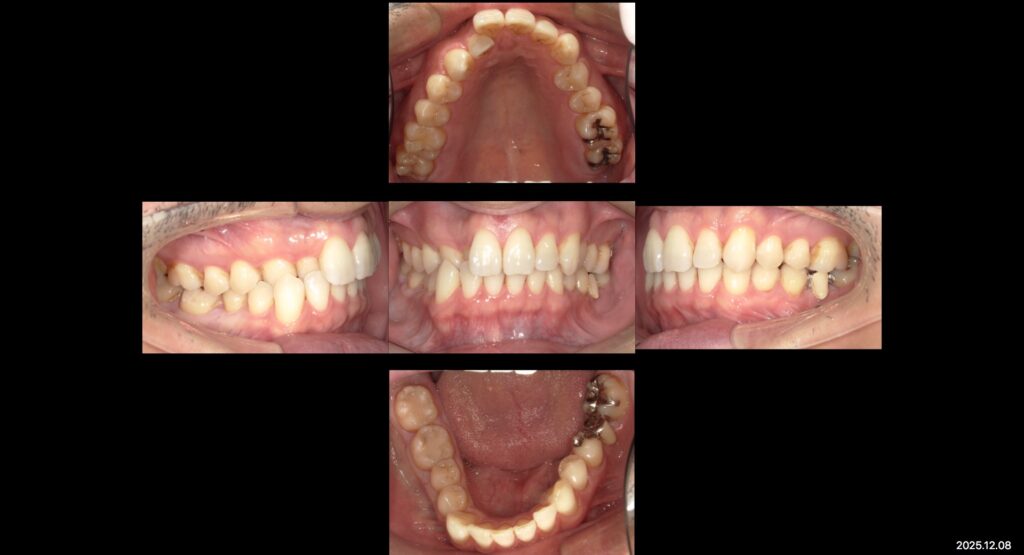

症例写真ー全顎治療ー

上:初診時口腔内写真

主訴

見た目をきれいにしたい

治療内容

矯正治療+補綴治療+インプラント+ホワイトニング

年齢

44歳

性別

男性

目的

欠損部治療と不適合補綴物のやり替えを咬み合わせ改善、審美や歯並びの見た目の改善

本日は全顎治療を終えた患者様の症例写真です✨

矯正治療や、虫歯治療、不適合補綴物のやりかえなど全顎的に根本治療を行いました。